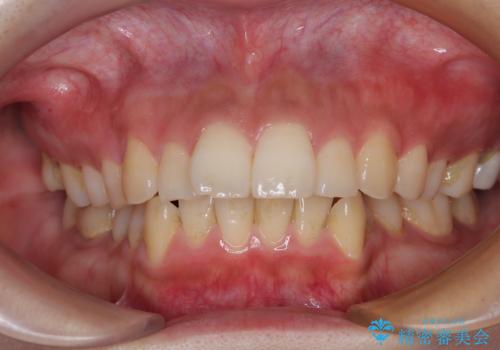

捻れて前に出ている前歯 ワイヤー装置での非抜歯矯正